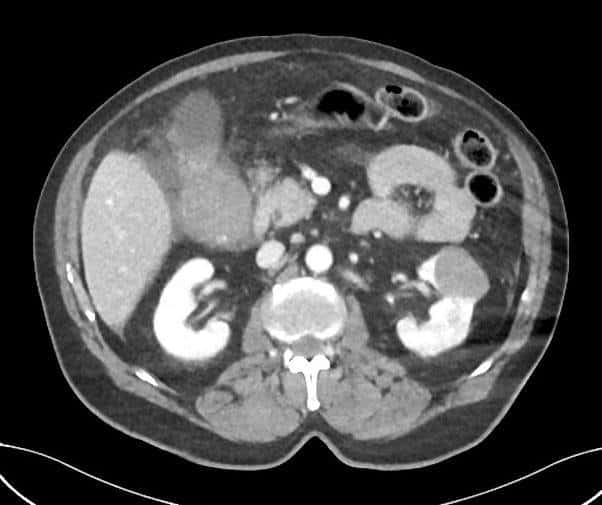

Vỡ túi mật

» Thông tin: Nam giới – 80 tuổi.

» Lâm sàng: Chấn thương.